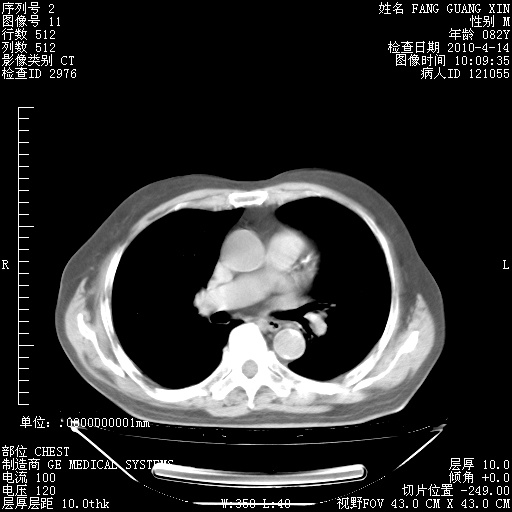

4月14日肺部CT

肺部CT平扫未见异常。